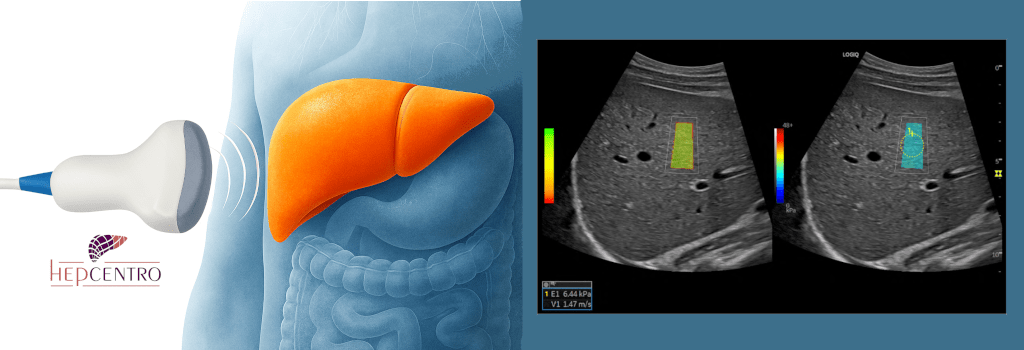

Exames de imagem tipicamente são pouco úteis para o diagnóstico da CBP, mas são necessários em todos os pacientes. Ultrassom, tomografia (com contraste) ou ressonância nuclear magnética (com contraste) servem para descartar nódulos, mostrar sinais de doença crônica ou cirrose e se há dilatação das vias biliares, que pode sugerir a presença de outras doenças, como cálculos ou tumores. Nem sempre esses exames mostram bem o estágio da doença, podendo-se associar exames de elastografia transitória ou ultrassônica. A colangioressonância é o exame de escolha para investigar as vias biliares, e geralmente é normal na CBP pois essa afeta apenas os canalículos biliares (os mais finos). Por outro lado, ajuda a diferenciar a CBP da colangite esclerosante primária, que afeta os canais maiores e aparece na colangioRM.